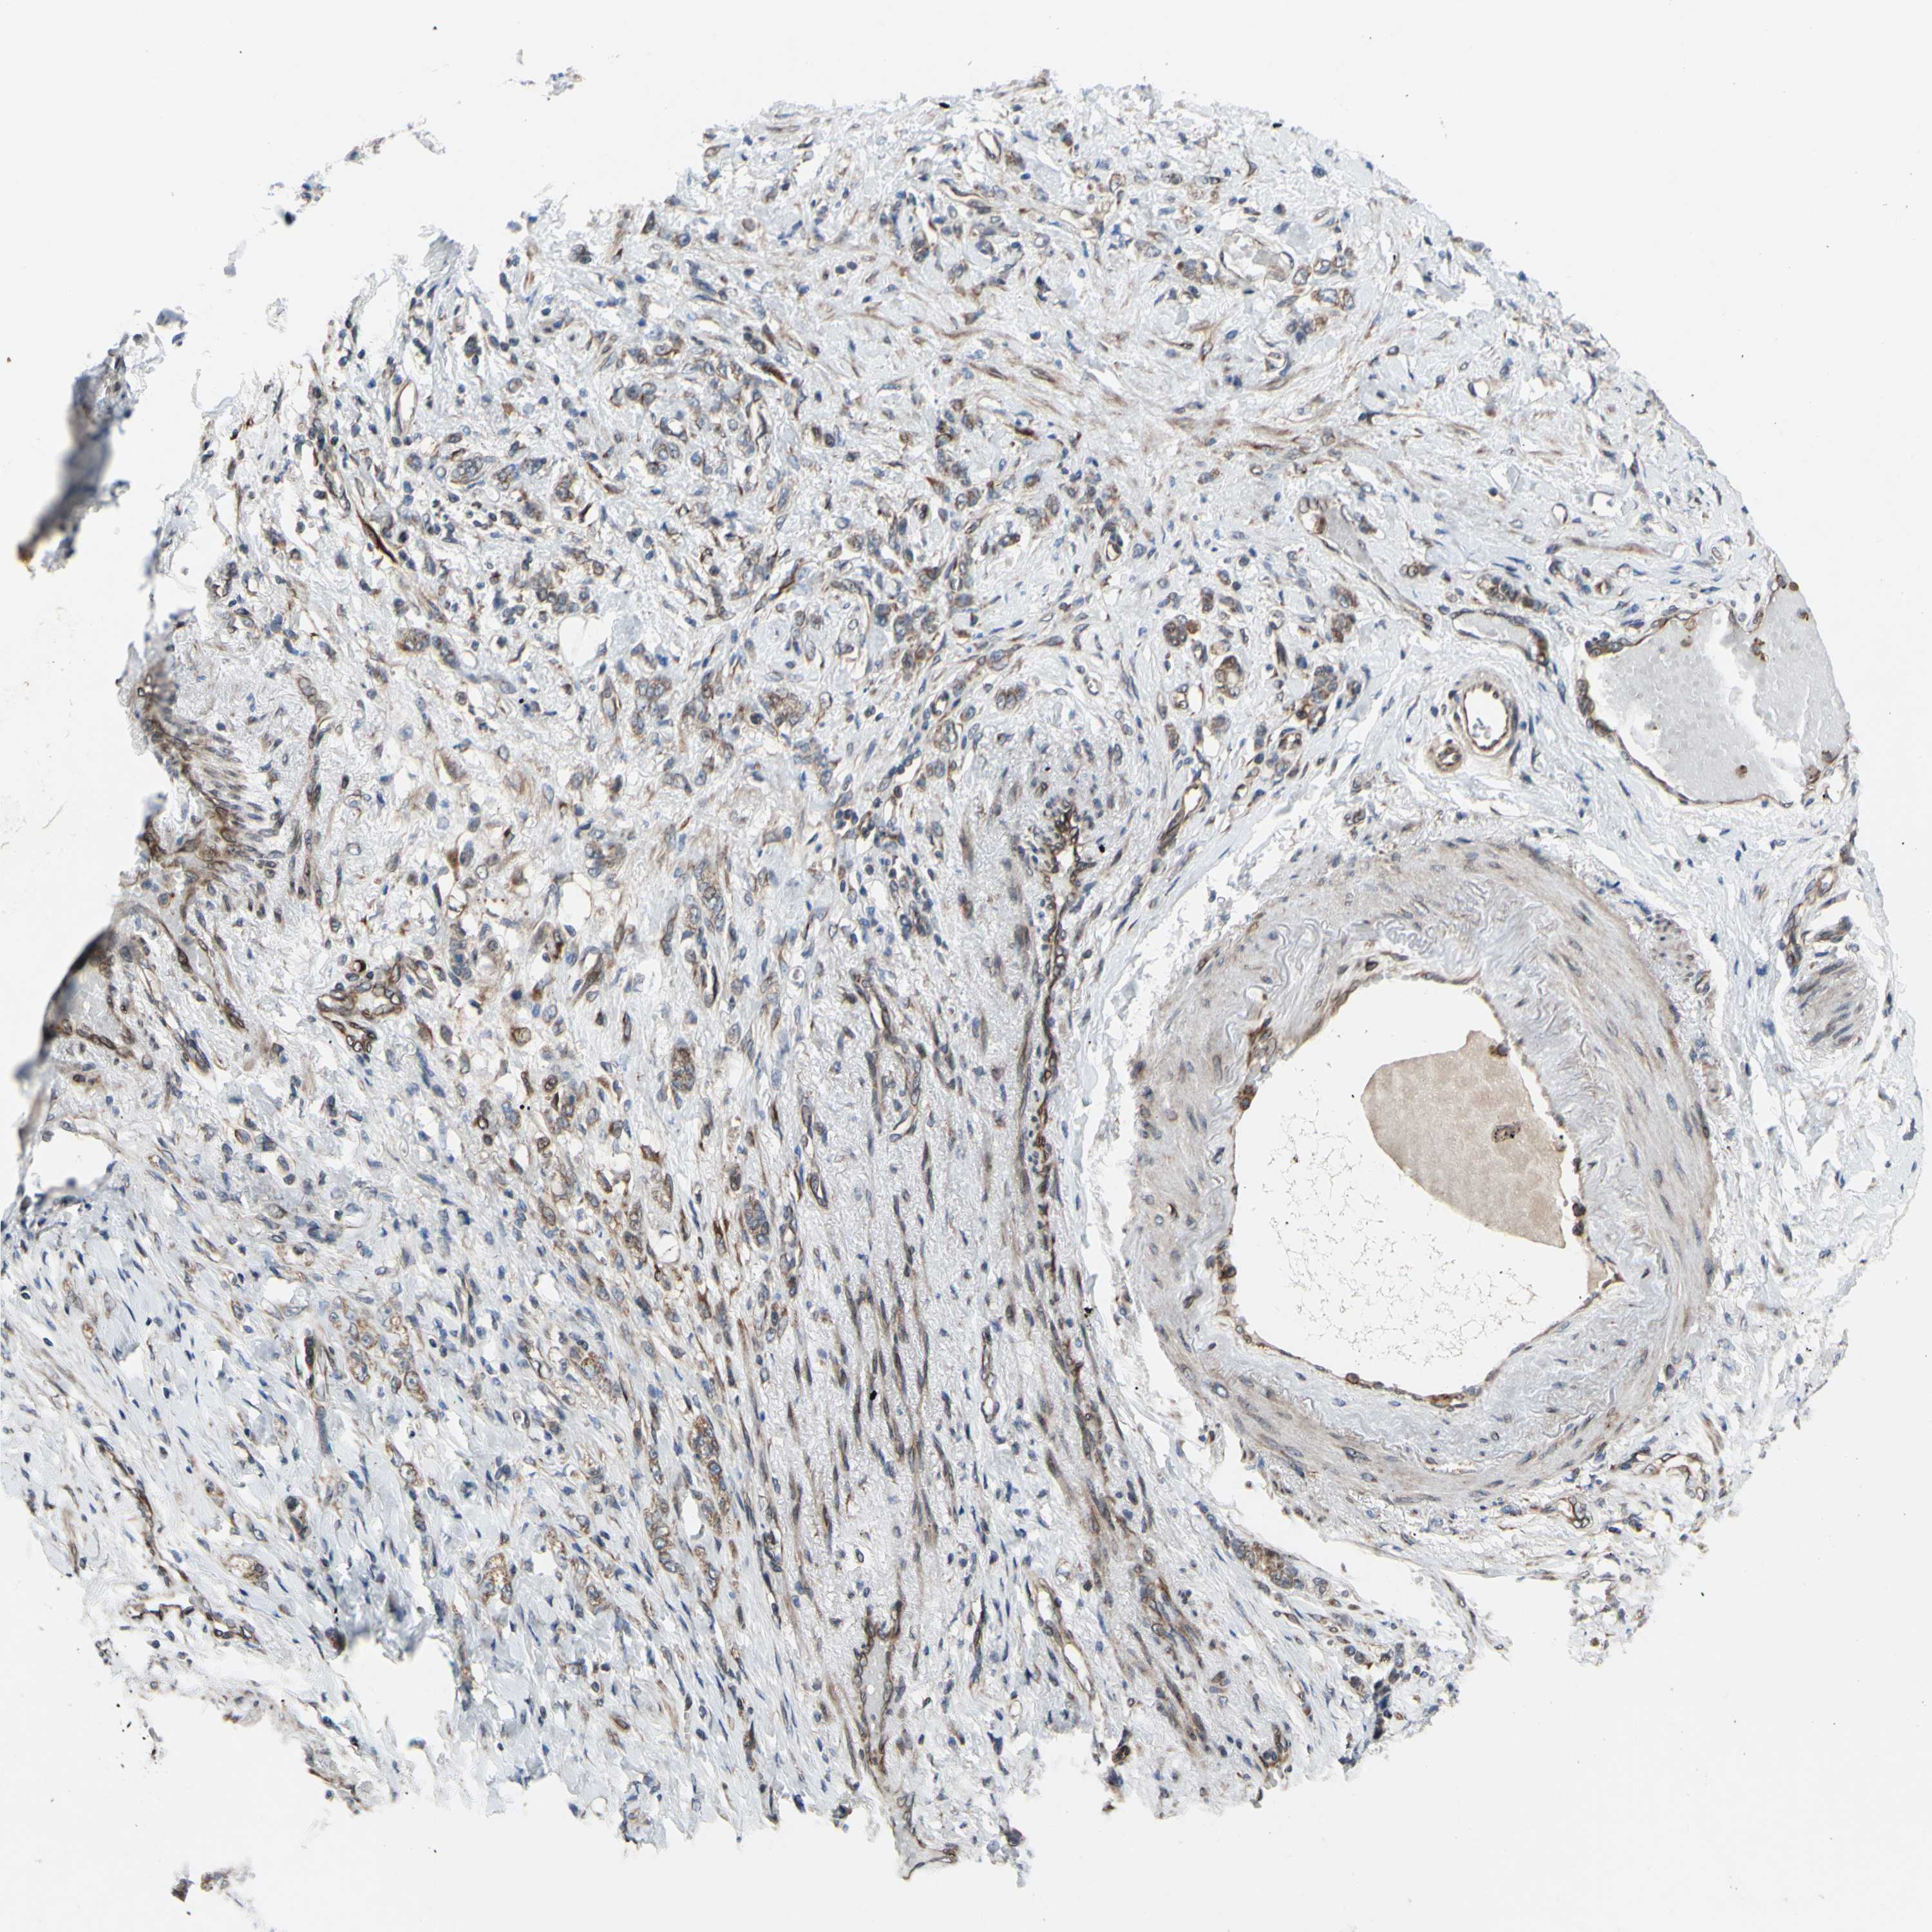

STOMACH CANCER - Protein expressioni

A mouse-over function shows sample information and annotation data. Click on an image to view it in a full screen mode. Samples can be filtered based on level of antibody staining by selecting one or several of the following categories: high, medium, low and not detected. The assay and annotation is described here.

Note that samples used for immunohistochemistry by the Human Protein Atlas do not correspond to samples in the TCGA dataset.

Antibody stainingi

Antibody staining in the annotated cell types in the current human tissue is reported as not detected, low, medium, or high, based on conventional immunohistochemistry profiling in selected tissues. This score is based on the combination of the staining intensity and fraction of stained cells.

Each image is clickable and will lead to virtual microscopy that enables deeper exploration of all samples and also displays staining intensity scores, fraction scores and subcellular localization as well as patient and tissue information for each sample.

Antibody HPA002859

Antibody CAB011655

Staining

High

Medium

Low

Not detected

Intensity

Strong

Moderate

Weak

Negative

Quantity

>75%

75%-25%

<25%

None

Location

Nuclear

Cytoplasmic/membranous

Cytoplasmic/membranous,nuclear

Adenocarcinoma, NOS

Adenocarcinoma, High grade